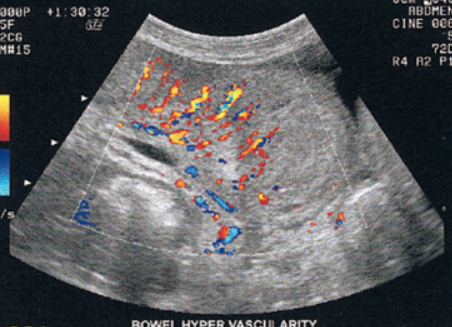

Bowel obstruction